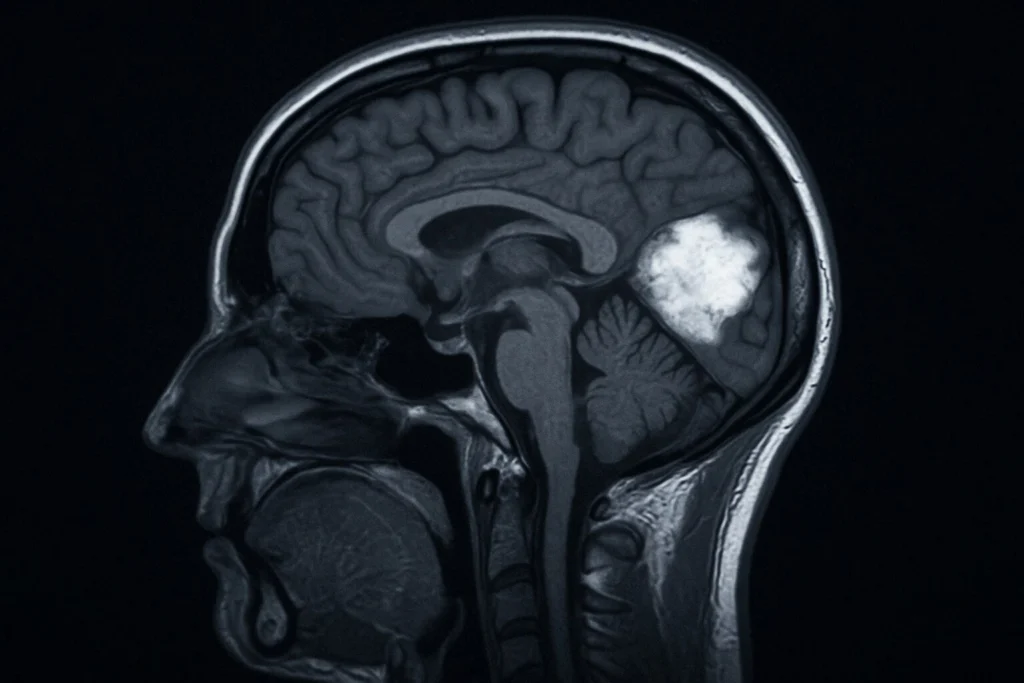

Un nuovo studio pubblicato dall’American Academy of Neurology ha rivelato una scoperta allarmante: bere otto o più drink alcolici a settimana può aumentare significativamente il rischio di sviluppare lesioni cerebrali e condizioni neurodegenerative, potenzialmente mettendo a rischio milioni di persone in tutto il mondo. La ricerca ha messo in evidenza una condizione chiamata arteriolosclerosi ialina, in cui i piccoli vasi sanguigni del cervello diventano rigidi, stretti e meno efficienti nel trasportare sangue. Questo deterioramento vascolare può portare alla formazione di lesioni cerebrali vascolari, che compromettono la memoria e le capacità cognitive.

Un ulteriore elemento preoccupante dello studio riguarda i cosiddetti “grovigli di tau”, un biomarcatore associato all’Alzheimer. I forti bevitori avevano una probabilità superiore del 41% di sviluppare queste anomalie cerebrali, mentre gli ex bevitori un 31% in più. Secondo il National Institute on Alcohol Abuse and Alcoholism, oltre 16 milioni di adulti statunitensi hanno riferito un consumo eccessivo di alcol nell’ultimo mese. Questo significa che milioni di persone potrebbero già essere a rischio.